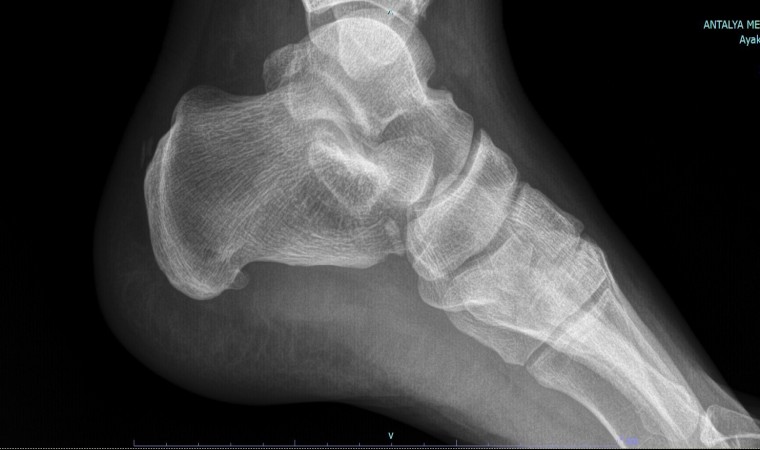

Tedavi yöntemleri hakkında da açıklamalarda bulunan Prof. Dr. Demiralp, “Ağrılı topuk sendromunun nedenlerine baktığımız zaman öncelikli olarak nedenini araştırmamız gerekir. Biz öncelikli olarak hastalarımızın şikayetlerini dinliyoruz. Ardından muayene yapıp gerekirse röntgen çekiyoruz. Burada en sık karşımıza çıkan plantar fascia dediğimiz ayakta gerginliktir. Ayakta yaşanan bu gerginliğin ardından uzun dönemde zarın çekmesiyle topuk kemiğinde uzaması sonucu gül dikenine benzer ince bir kemik yapı oluşturur” sözlerine yer verdi.

Hastanın iki dakikalık botoks yöntemi ile sağlığına kavuştuğunu belirten Prof. Dr. Demiralp, “Çeşitli tedavi yöntemleri olsa da biz daha çok botoks tedavisini tercih ediyoruz. Bu uygulama diğerlerine göre daha konforlu ve daha kısa sürede sonuç alabiliyoruz. Hastamızı muayene edip filmlerini gördükten sonra enjeksiyona karar verirsek, eğer tıbbı bir problemi yoksa botoks uygulamasını gerçekleştiriyoruz. Hastamıza uygun bir doz seçerek topuğa çok ince bir iğneyle botoks enjeksiyonu yapıyoruz. Amacımız gerginliğe sebep olan, topuk dikenine sebep olan Plantar Fasiitin gevşetilmesidir. Hasta birkaç gün içerisinde bu gevşemenin farkına varıyor. Ağrısı azalıyor. Çok uzun süre ağrısız bir dönem geçirebilir. Hastamız hemen normal hayatına dönebiliyor. Hiçbir kısıtlamamız yok. Cerrahi yöntemde ise hasta en az 2-3 hafta hayatını kısıtlayabilir. Her zaman cerrahiye ihtiyaç yoktur” açıklamasına yer verdi.